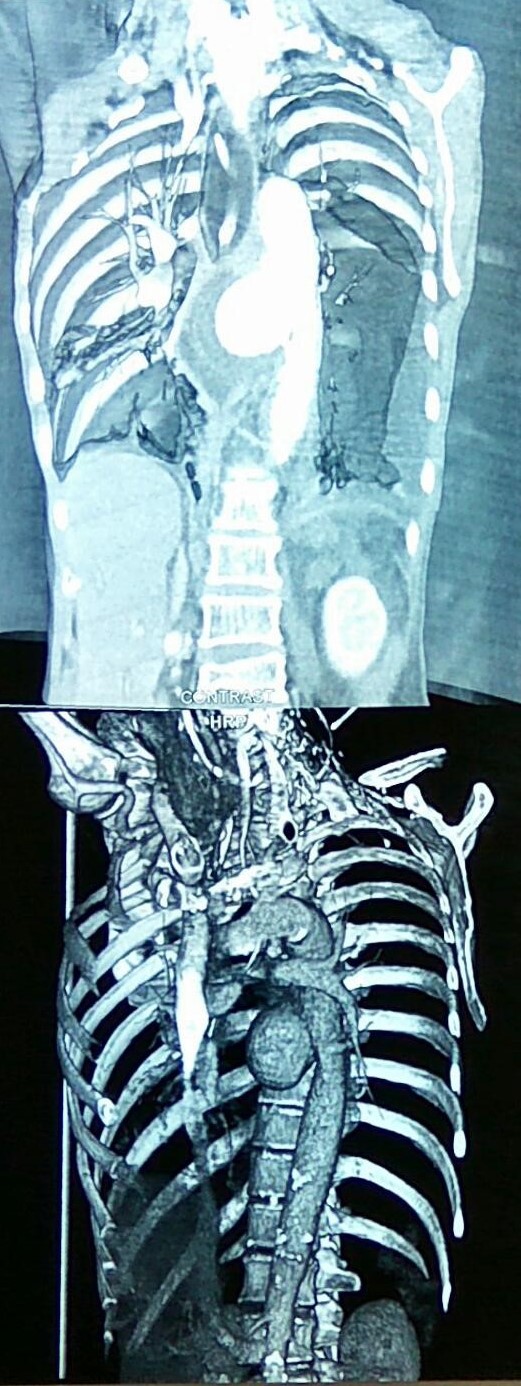

CT Αγγειογραφία. Πράσινο βέλος αιμάτωμα. Οριζόντιο κόκκινο βέλος stent στο AAA. Κατακόρυφο κόκκινο βέλος ψευδοανεύρυσμα τόξου Riolan (Ευγενική παραχώρηση Dr. V. Penopoulos)